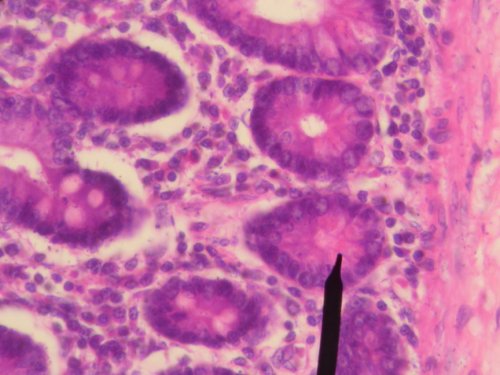

14. Наши клетки никогда не перестают воспроизводиться

Клетки являются строительными блоками организма. Каждую секунду человеческое тело производит 25 миллионов новых клеток. Для сравнения, за каждые 13 секунд клеток вырабатывается больше, чем численность населения США.

11. Большинство наших клеток не являются человеческими

Из миллиардов клеток, составляющих человеческое тело, лишь около 10 процентов на самом деле «человеческие». Остальные 90 процентов состоят из различных грибков и бактерий.